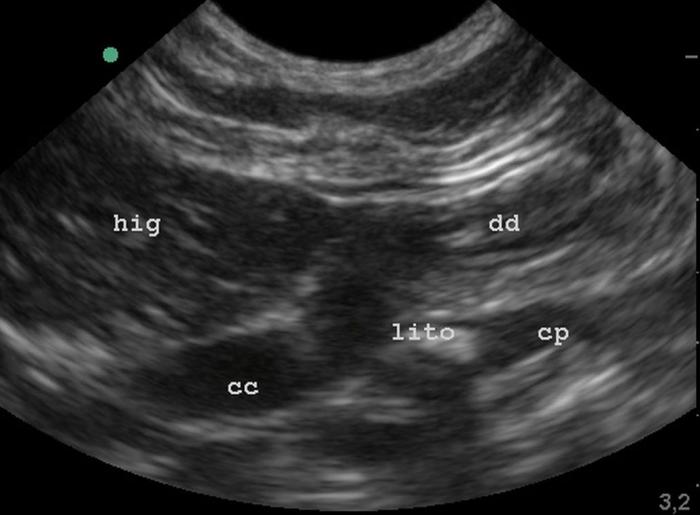

Se trató de otro paciente felino de 10 años de edad, que padecía desde hace algún tiempo de triaditis felina, presentando períodos asintomáticos, con reagudizaciones esporádicas. En una reagudización se le realizaron estudios de sangre (Figura 7), obteniéndose amilasa y colesterol elevados, y un estudio ultrasonográfico, en la cual se detectaron signos compatibles con pancreatitis crónica y un cálculo semiobstructivo en el conducto pancreático (Figuras 8 y 9).

En otra toma ultrasonográfica se reconoció que el cálculo se ubicaba en la región del esfinter de Oddi, e indirectamente afectaba al conducto colédoco (Figura 10).

La ultrasonografía del caso 2 fue realizada utilizando un equipo marca Sonosite® modelo M-Turbo®, con transductores microconvexo de 5 a 9 MHz y lineal de 8 a 15 MHz.

El hallazgo ecográfico de estructuras hiperecogénicas intraductales con sombra acústica posterior, asociado a la dilatación del conducto pancreático, fue fundamental para la sospecha diagnóstica de litiasis pancreática. Esta combinación ha sido descrita previamente como una de las principales herramientas de diagnóstico por imagen en casos de pancreatolitiasis felina9,10. El uso de Doppler color, que permite identificar artefactos de centelleo o twinkling, ha demostrado aumentar la sensibilidad para detectar minerales intraductales como el carbonato de calcio11.

Los signos clínicos observados, como ictericia, pérdida de peso y vómitos crónicos, deben ser considerados como alertas diagnósticas, particularmente si se acompañan de hallazgos ecográficos como dilatación del conducto pancreático o estructuras hiperecogénicas con sombra acústica posterior10,11. La ecografía transabdominal, especialmente combinada con Doppler color, constituye una herramienta fundamental para la sospecha de litiasis intrapancreática, aunque su confirmación definitiva sigue dependiendo frecuentemente de evaluaciones post mortem9.